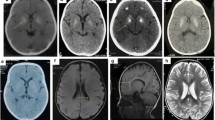

All affected individuals in whom MR imaging was available (9/12) showed hypomyelination, with T1 hyperintense or isointense signal, and T2 hyperintensity diffusely involving the cerebral white matter including the arcuate fibers, the internal capsule, and the corpus callosum (Fig. 1), though in some individuals, these were spared. The basal ganglia, brainstem, and cerebellum were relatively spared, though signal abnormalities were seen in the middle and superior cerebellar peduncles and in some individuals also the hilus of the dentate. There was mild loss of white matter volume and thinning of the corpus callosum, without evident volume loss of basal ganglia and cerebellum. No abnormalities were evident on susceptibility-weighted images or diffusion-weighted images, where available. No contrast enhancement was seen where available.

MRI findings in H-SMD. Axial T2-weighted images (a–c, e–g, i–k) and sagittal T1-weighted images (d, h, l) of patient 7 at age 4 years (first row), patient 8 at age 5 years (second row), and patient 1 at age 4 years (third row). The supratentorial white matter shows a diffusely elevated T2 signal (b, c, f, g, j, k), with unremarkable T1 signal (d, h, l) indicating hypomyelination. Signal of the basal ganglia is normal (b, f, j). The cerebellum has a normal volume (a, d, e, h, i, l). Signal of the superior cerebellar peduncles is hyperintense in all patients (a, e, i). Patient 7 has also signal elevation of the hilus of the dentate nucleus (a). Patient 8 of the external part of the middle cerebellar peduncle (e). Patient 1 has relatively better myelination of the brainstem, corpus callosum and deep gray nuclei